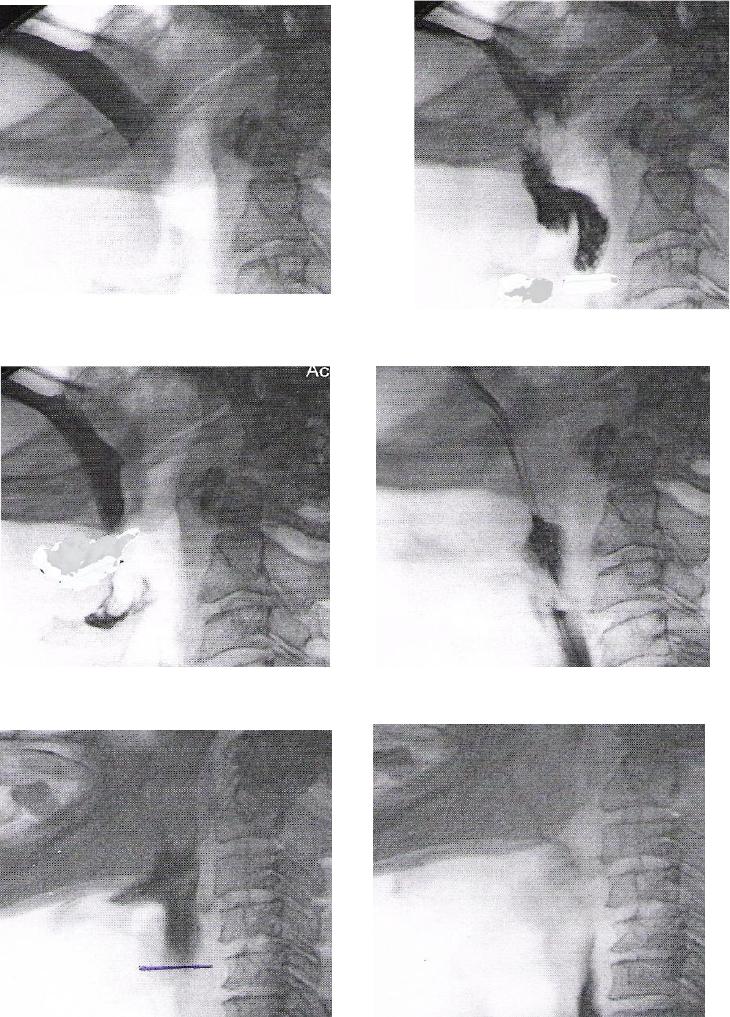

ANEXO E Imagens videofluoroscópicas da deglutição, registrando

escape prematuro e reação de deglutição atrasada, p e s

crioestimulação, com líquido e pastoso.........................................................